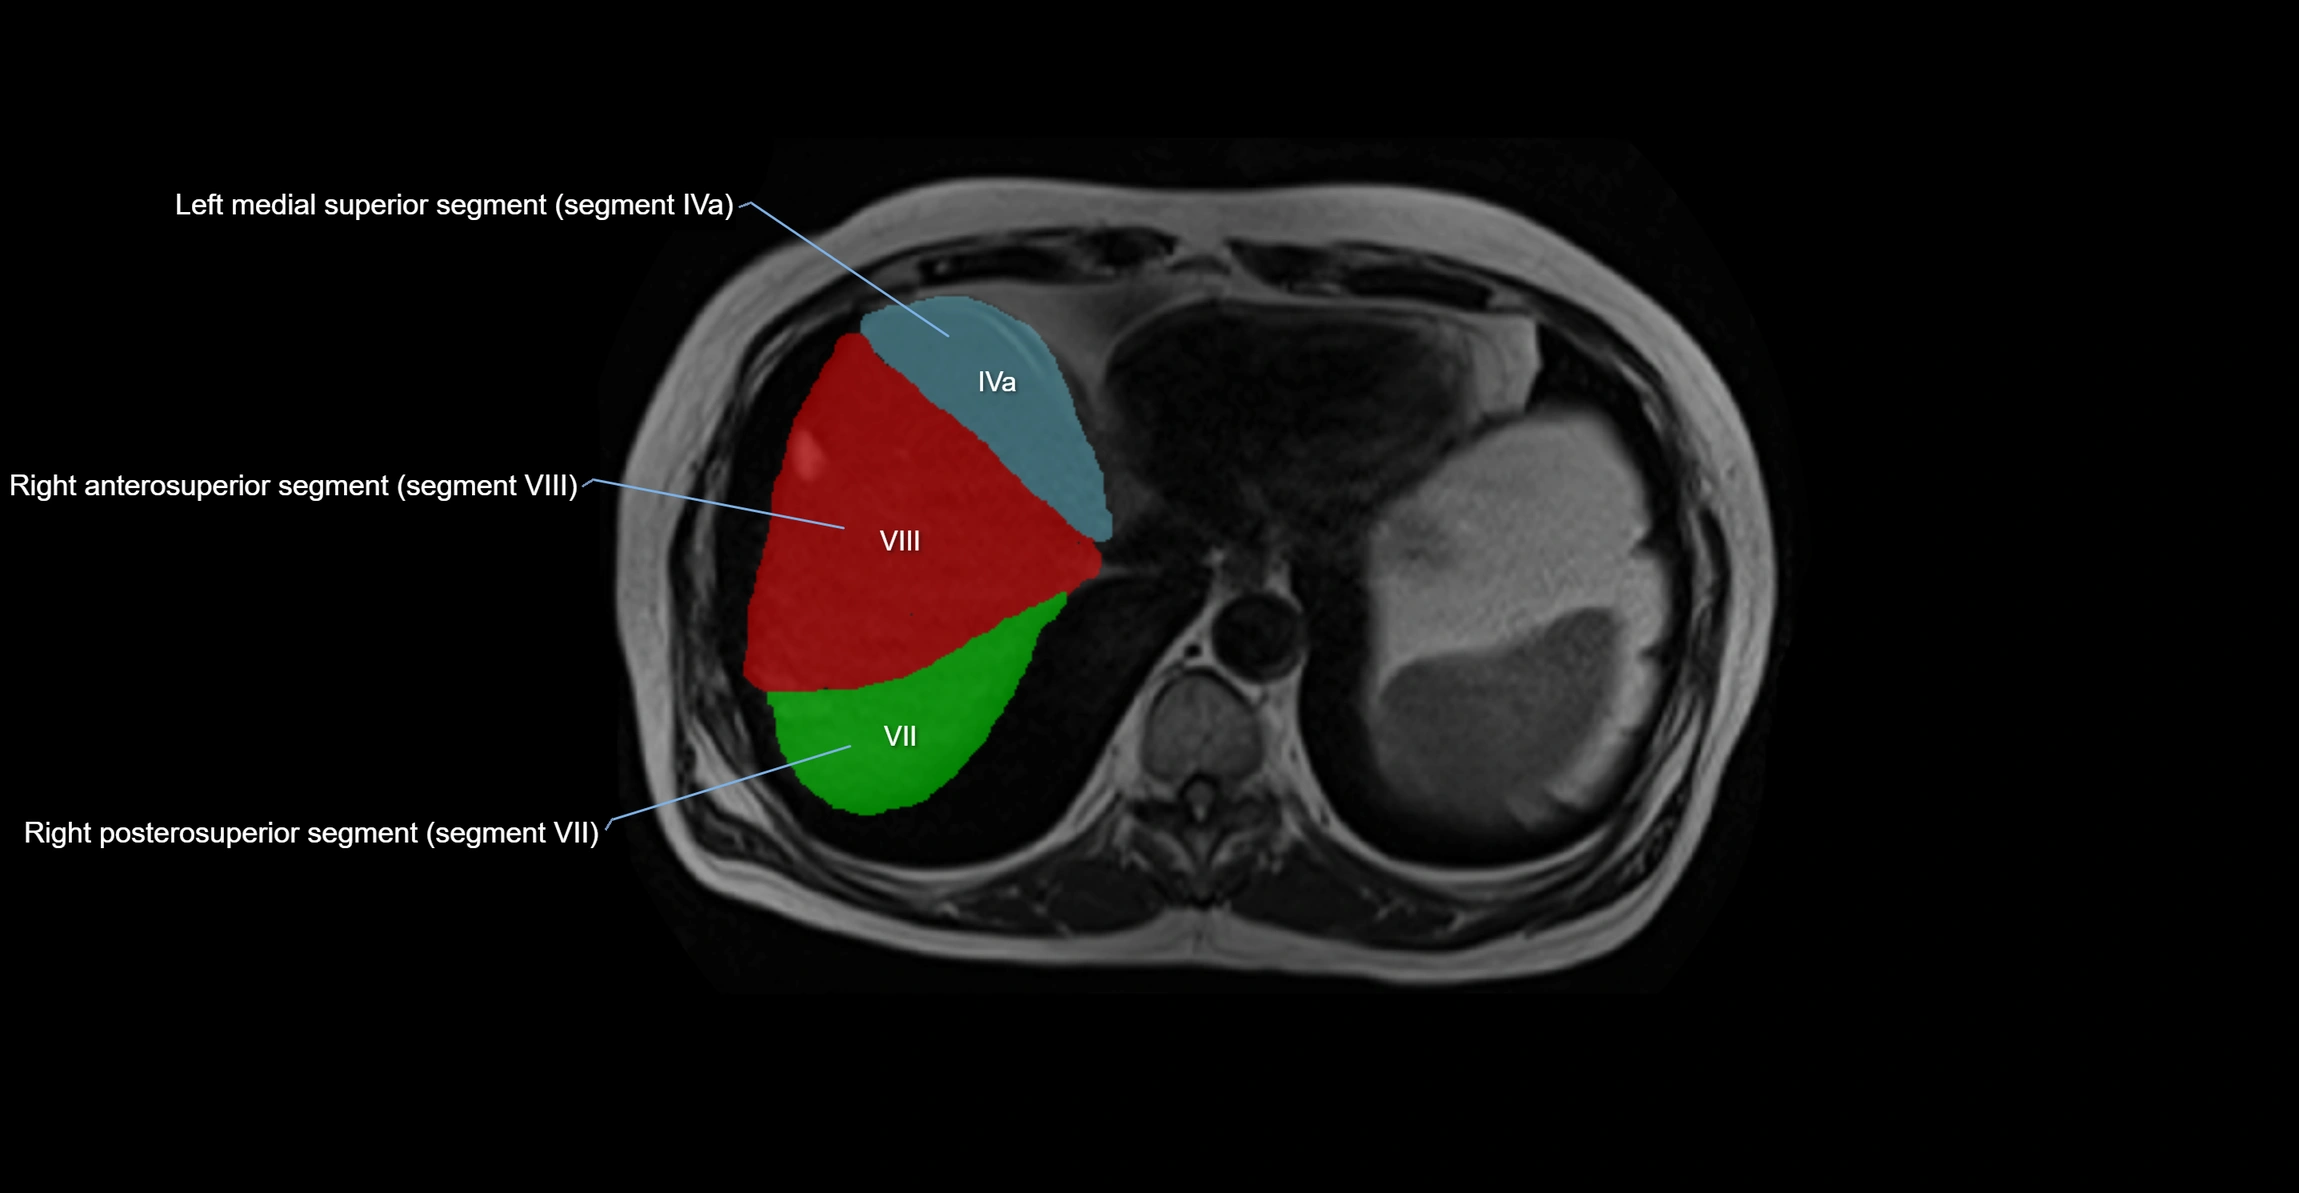

The caudate lobe of the liver is a distinct anatomical subdivision of the liver, designated as segment I in Couinaud’s classification. It lies on the posterior surface of the liver, between the fissure for the ligamentum venosum (left boundary) and the groove for the inferior vena cava (IVC) (right boundary). Superiorly, it is related to the posterior liver surface, and inferiorly it is separated from the left lobe by the porta hepatis.

The caudate lobe is unique because it receives dual portal venous and arterial inflow from both the right and left portal veins and hepatic arteries. It also has independent venous drainage directly into the IVC via multiple small hepatic veins, unlike other lobes that drain through the three main hepatic veins.

This anatomical autonomy makes the caudate lobe especially significant in liver surgery, transplantation, and hepatic venous outflow obstruction syndromes (e.g., Budd–Chiari syndrome). Enlargement of the caudate lobe is a characteristic imaging feature in chronic liver disease and cirrhosis.